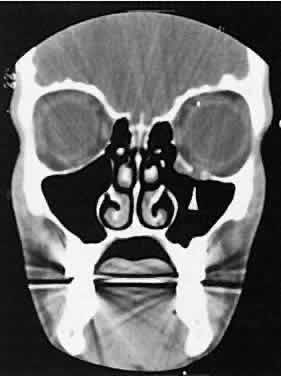

Nonspecific inflammatory dacryoadenitis shows enlargement of the lacrimal gland, which typically molds to the shape of the globe (Fig. 6). The adjacent bone is normal, and contrast enhancement of the gland usually is fairly homogeneous. Bilateral involvement may be apparent with certain conditions such as Sjogren's syndrome, sarcoidosis, lymphoma, or even Graves' orbitopathy, although enlarged EOM in the latter condition might make this a more obvious diagnosis.

Fig. 6. Nonspecific inflammatory dacryoadenitis. An isodense enlargement of the lacrimal gland is noted on axial (A) and coronal (B) views. Note the similarity to Figure 18.